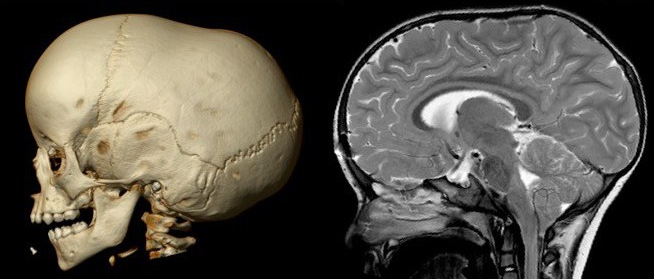

Morphologiquement, il existe un bombement frontal médian associé à un pincement temporal, ainsi qu’un boulet occipital. l’indice céphalique est inférieur à 75%. Le périmètre crânien et en général à la limite supérieure de la normale, voire nettement au dessus car le volume intracrânien est préservé alors que le crâne est allongé. il existe souvent un dysharmonie dento-faciale car le maxillaire en entraîné vers l’avant par l’allongement de la base du crâne (cf. ci-dessus).

le scanner est nécessaire pour s’assurer de l’absence de fermeture d’une autre suture et de la normalité du contenu crânien.